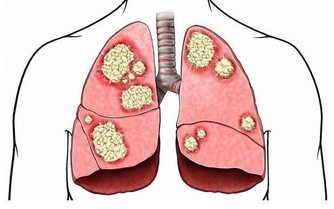

十二、體檢非常重要

現在的醫療發展已經可以治療相當多的疾病,也儘管還有許多疾病無法治愈,但可以依靠藥物和其他治療方法延緩進展。不過,這些療法和治療效果有一個共同特點:越早診斷和開始治療效果越好,所以體檢發現的疾病萌芽,往往可以在發病初期被治愈或者控制,哪怕是癌症。等到了有症狀再去看醫生,很多疾病實際上已經進入末期了。